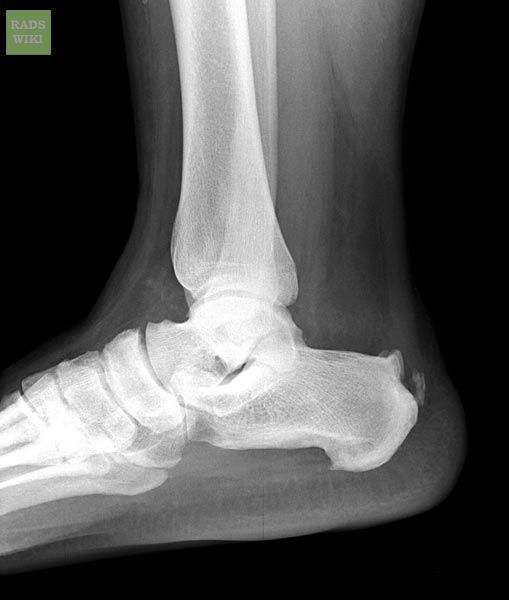

A heel spur is a calcium deposit causing a bony protrusion on the underside of the heel bone. On an X-ray, a heel spur can extend forward by as much as a half-inch. Without visible X-ray evidence, the condition is sometimes known as “heel spur syndrome.”